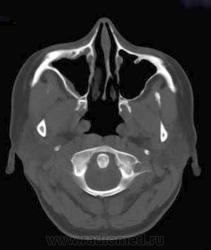

1. Эктопия зуба?

2. Хронический гайморит?